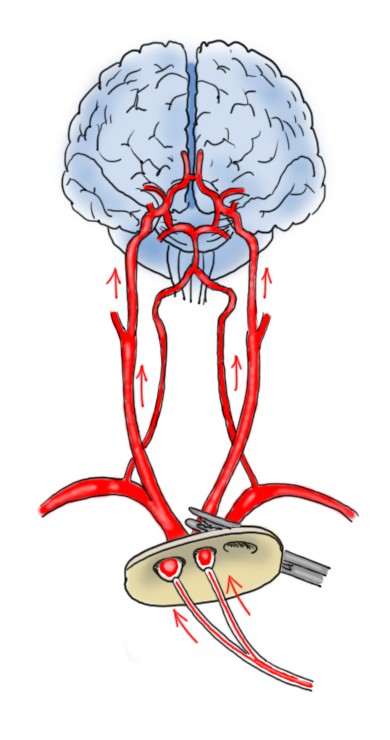

L’utilizzo dell’arteria ascellare destra (cannulata al solco deltoido-pettorale) per la connessione alla macchina cuore polmonare rende possibile la perfusione cerebrale anterograda selettiva monolaterale. In questa procedura, durante l’arresto ipotermico il tronco arterioso anonimo viene clampato (occluso). La macchina cuore-polmone viene fatta ripartire a un flusso di 10 ml/kg/min che – per via dell’occlusione del tronco arterioso anonimo – viene deviato lungo l’arteria carotide comune e lungo l’arteria vertebrale e perfonde in modo fisiologico l’emisfero destro del cervello. Se il poligono di Willis è pervio, il flusso di sangue raggiungerà anche l’emisfero di sinistra. Questo è confermabile visivamente dalla fuoriuscita di sangue dall’ostio delle arterie carotide comune di destra e ascellare di destra (che subito dopo andranno clampate per migliorare la perfusione cerebrale), ma soprattutto da metodiche non invasive di monitoraggio dell’ossigenazione regionale cerebrale (NIRS, Near-Infrared Spectroscopy). Se si dovesse sospettare che l’ossigenazione nel lato sinistro è carente, è necessario aggiungere la perfusione selettiva dell’arteria carotide di sinistra.